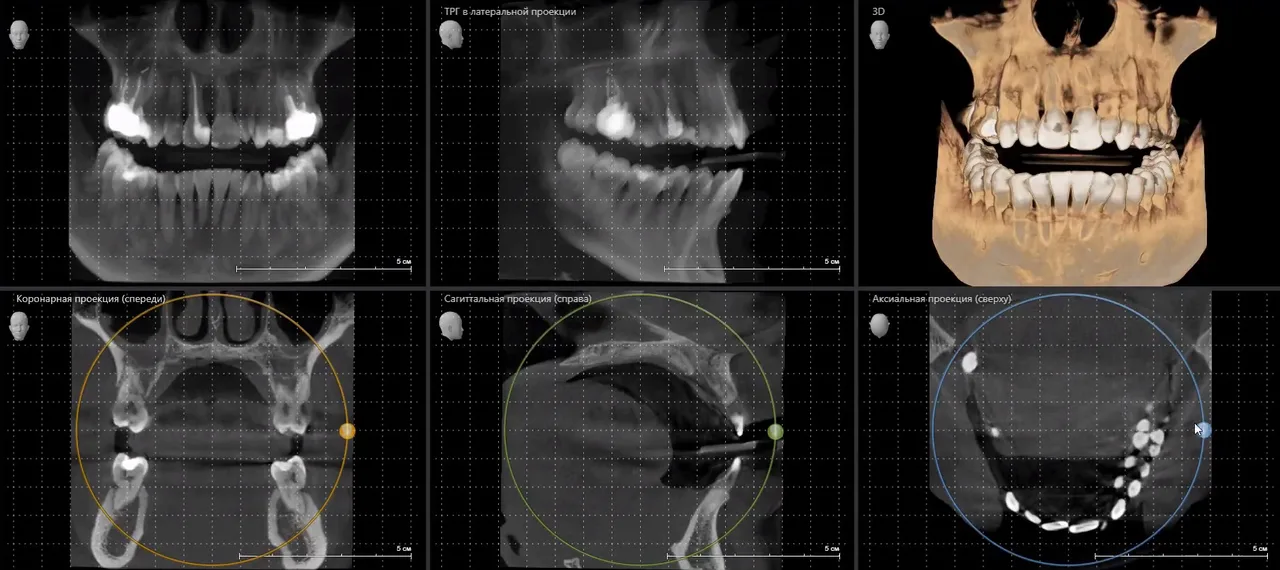

Компьютерная томография (КТ) зубов — это один из самых точных и информативных методов диагностики в современной стоматологии. С помощью специального оборудования создается объемное изображение челюстно-лицевой области, позволяющее врачу оценить состояние зубов, корней, костной ткани, а также выявить скрытые патологии. Отличие КТ от традиционного рентгена заключается в трехмерной визуализации, которая обеспечивает высокую точность диагностики и минимизирует вероятность ошибки.

Использование компьютерной томографии дает врачу намного больше информации по сравнению с панорамными или прицельными снимками. Основные преимущества КТ:

- возможность многоплоскостного анализа анатомии;